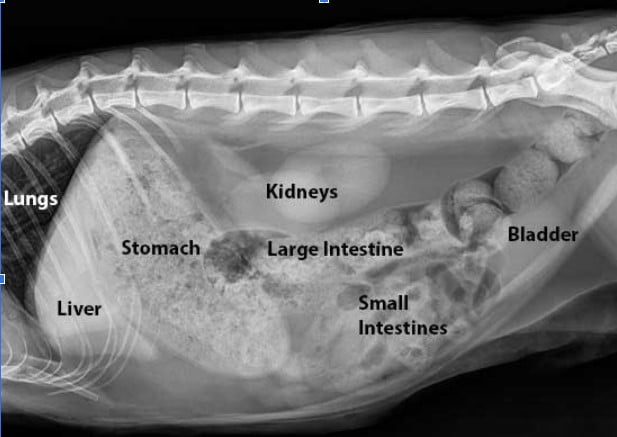

- X-rays pass through the body

- Bones and metal will absorb more X-ray radiation and be seen as appearing white on an X-ray image.

- Softer tissue will absorb less X-ray radiation and will be seen as gray

- Any areas of air within the body will show as black on an X-ray image.

Abdominal Conditions

- Bowel obstructions and/or foreign material

- Stones in the bladder

- Enlarged organs

- Evaluation of pregnancy